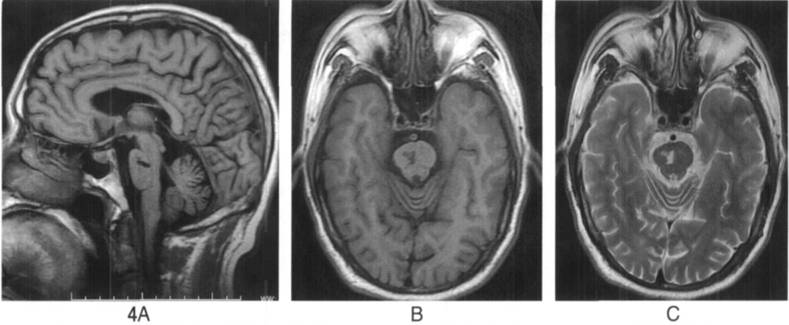

矢状位(A)及横断位B)T1WI显示脑干管状低信号灶;

C.T2WI显示脑脊液样高信号灶